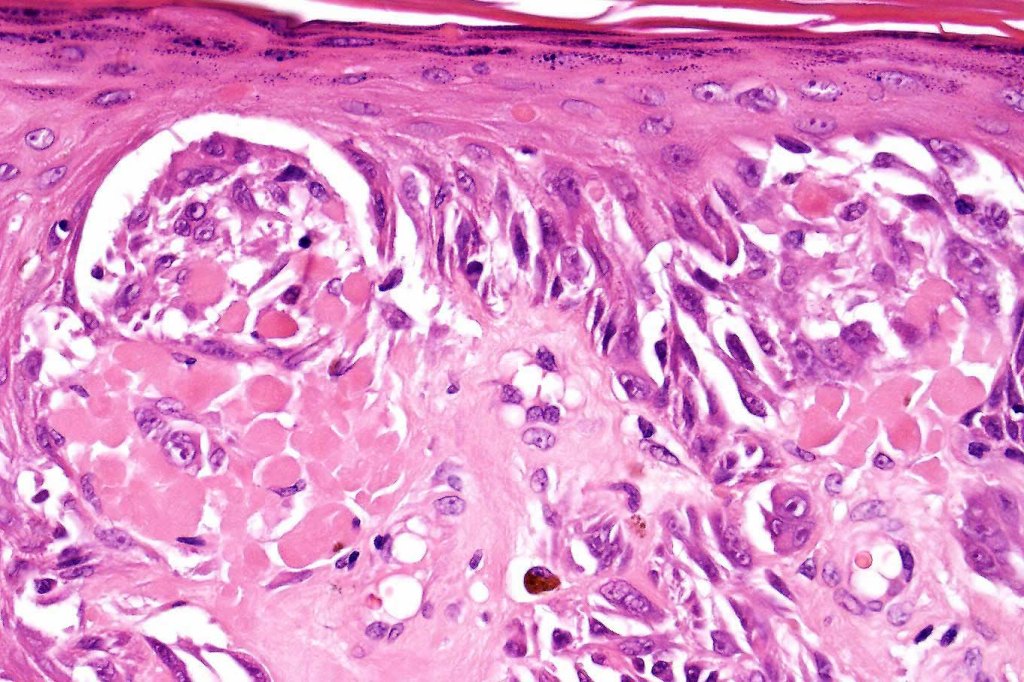

•Epithelioid cell variants often show greater pleomorphism and cells can frequently appear bizarre with abundant, sometimes ground glass cytoplasm and large vesicular nuclei with prominent eosinophilic nucleoli, multinucleate cells are often seen

•Intracytoplasmic pseudoinclusions commonly present in epithelioid cells

•Kamino bodies (often multiple) are a characteristic feature